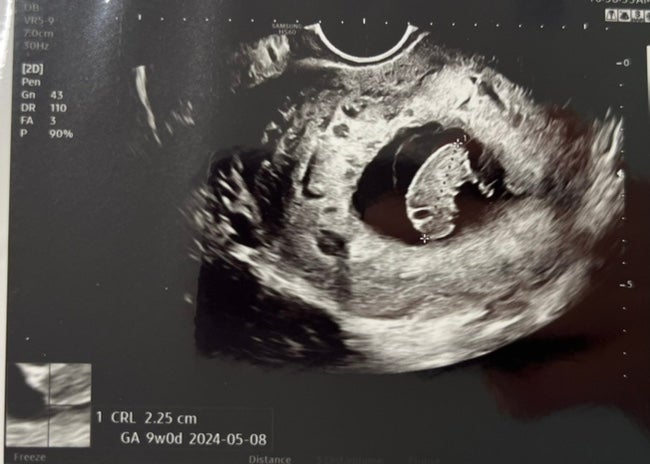

임신11주 - 니프티검사, 정밀초음파(일신기독병원)

안녕하세요 miaaa입니다☺️ 11주 5일이 되는 날, 기형아검사와 정밀 초음파를 하기 위해 병원에 방문했어...